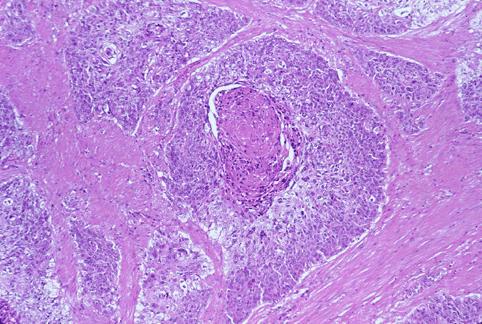

疾病(病理主体)的分类恶性上皮肿瘤/腺扁平上皮癌

部位(按器官分)大肠/直肠

检查方法病理切片(微观)

肿瘤最大直径40以上

肿瘤的深度ss(a1)